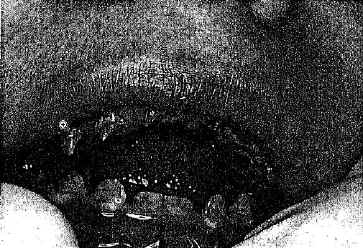

Die Zahnbildung war von Beginn an gelb und zackig (Abb.1). Alle

Abb.1 Amelogenese imperfecta

(Hypomineralisierung): reduzierte Zähne gelblicher Färbung mit weissen oder

braunen Kalkeinlagerungen. Allgemeiner Zahnschmelzverlust als Ergebnis von

mechanischer Abreibung oder chemischen Einflusses durch Speichel oder Nahrung,

besonders an der labialen Oberfläche und an den Molaren. Man beachte den

verbliebenen Zahnschmelz über den vorderen Zahnhälsen. (3-½ jähriger

Junge)